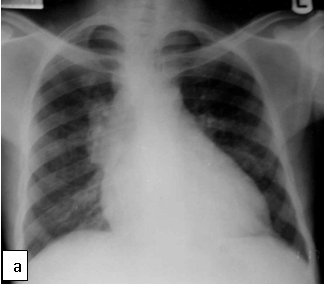

Chest X-ray (CXR): TB enlarged perihilar lymph nodes are better visualised on a lateral CXR than a PA view, therefore, it is important to obtain both PA and lateral films when evaluating a child with suspected TB.